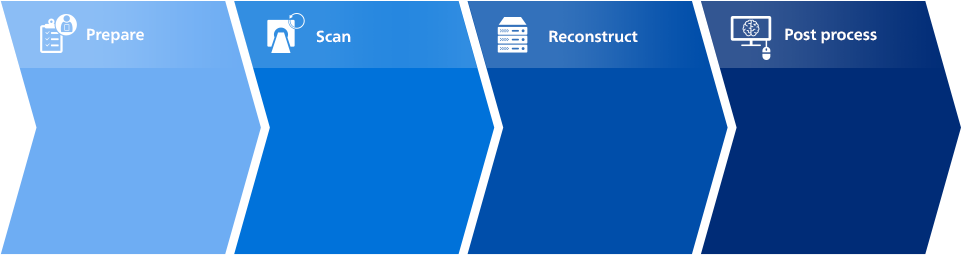

See how CT Smart Workflow assists your team at every step

See how Smart Workflow assists your team with smarter workflow at every step